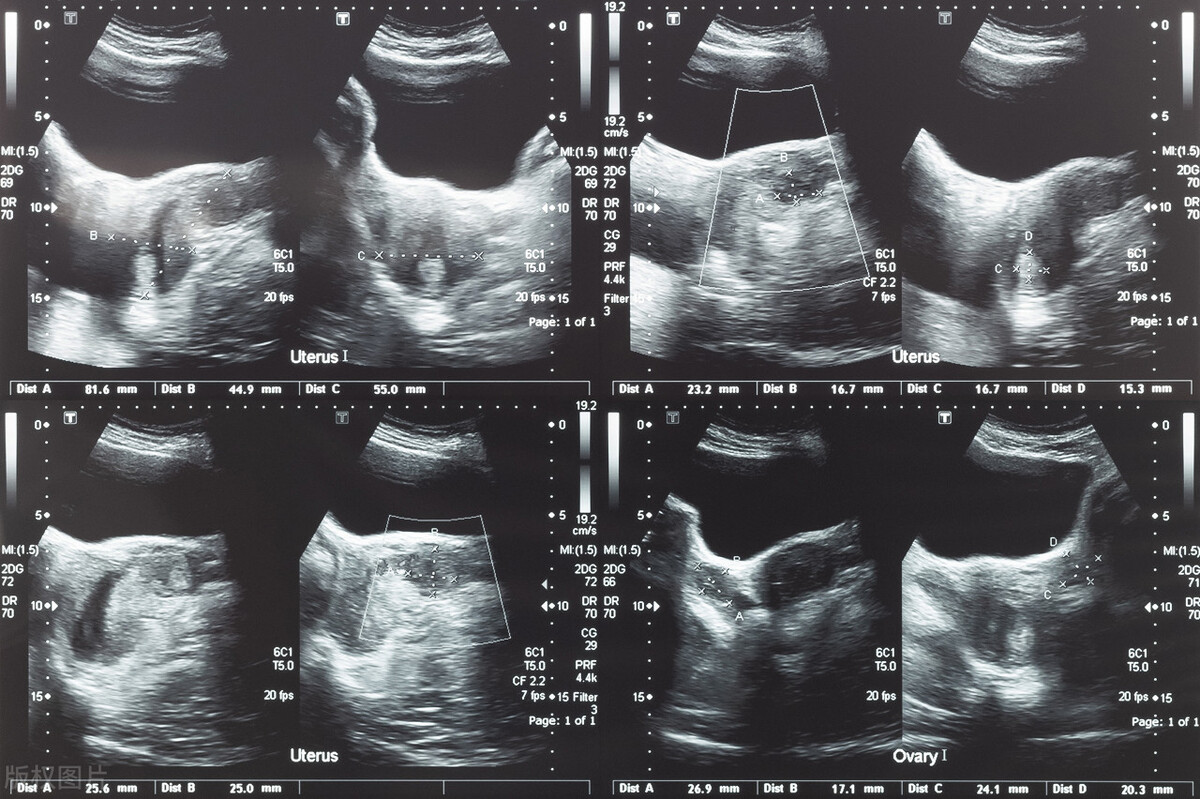

在选择中医治疗时,需要注意的是,对于已经有手术指征的患者,建议先手术,而不要直接使用中药进行治疗。在中医治疗的过程中,b超也要定期复查。如果子宫肌瘤迅速增大,月经过多出现贫血症状,应及时手术。

如果子宫肌瘤直径在三厘米左右,可以用药物保守治疗。如果超过五厘米,就需要进行手术来治疗。